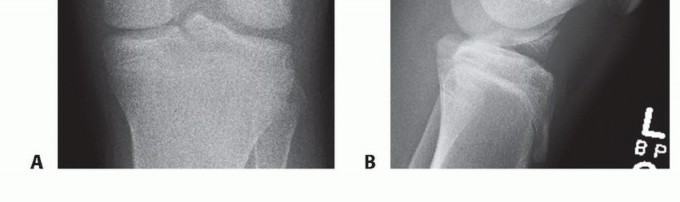

In lesions that are predominantly cartilaginous, radiographs may sometimes detect a small piece or a fleck of avulsed bone, which may be indicative of the avulsed osteochondral fragment, and underestimate the true size of the fracture fragment (FIG 4).

FIG 4 • AP (A) and lateral (B) radiographs of the knee showing a displaced tibial spine fracture (type III).*